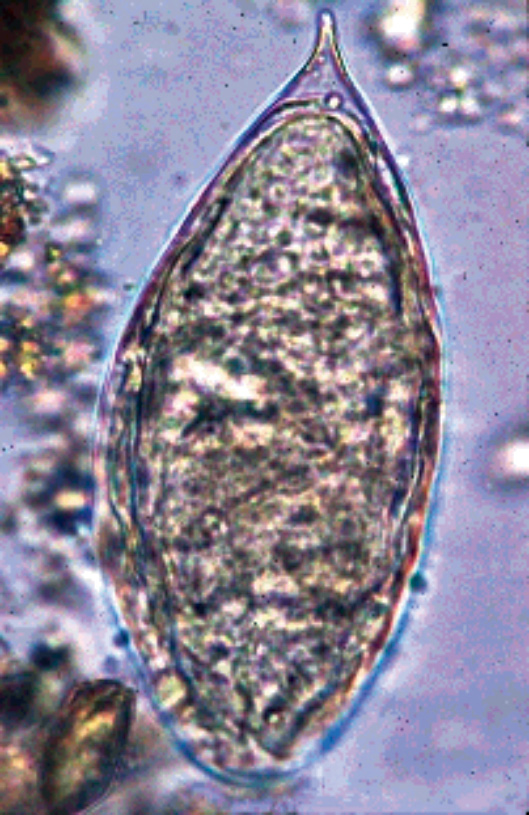

図1.主要な住血吸虫3種における虫卵

感染動物はビルハルツ住血吸虫ではヒト、マンソン住血吸虫では齧歯類やヒヒ、日本住血吸虫ではウマやイヌなどを含む多くの動物である。ヒトを含む感染動物が尿や便中に虫卵を排泄するが、虫卵のサイズはビルハルツ、マンソン住血吸虫では110~170×40~70μmであり、前者の場合先端部に(図1a)、後者の場合一側に棘を有する(図1b)。日本住血吸虫卵は80~100×40~60μmで長径がやや短く、楕円形で側面に小棘を有する(図1c)。メコン住血吸虫卵は日本住血吸虫卵に、インターカラーツム住血吸虫卵はビルハルツ住血吸虫卵に類似する。虫卵の中にはミラシジウムが形成されるが、これが水中で中間宿主としての淡水産貝に侵入する。それぞれの住血吸虫は異なる淡水産貝に寄生するが、ビルハルツおよびインターカラーツム住血吸虫ではBulinus属、マンソン住血吸虫ではBiomphalaria属、日本住血吸虫ではOncomelania属(宮入貝)、メコン住血吸虫ではTricula apertaである。淡水産貝の中ではスポロシストを経て、セルカリアに成長する。セルカリアは約0.3mmの長さで二分した尾部を持つが、これが淡水中を遊泳し、ヒトの皮膚を貫通して血中に侵入する。その後、ヒト体内で肺を通過してから静脈に定着するが、シストソミュールのステージを経て成虫となる。